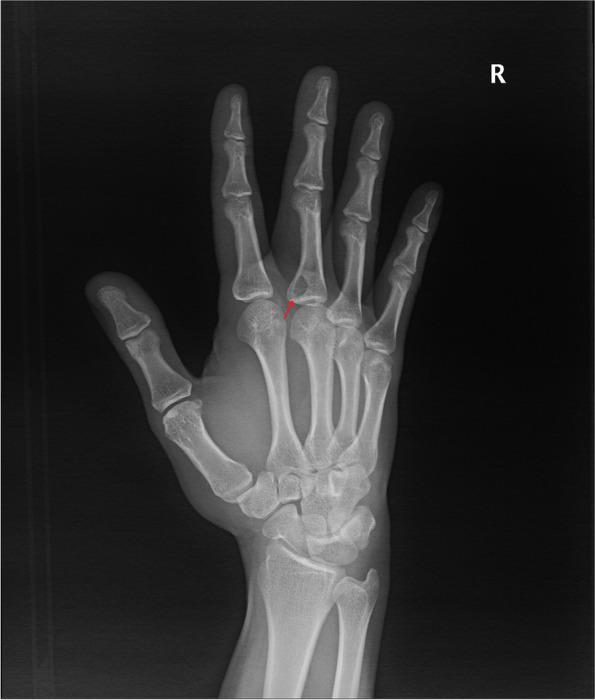

Fifteen patients who underwent surgical treatment were enrolled in this study. There were seven cases in the upper extremities, four in the trunk area, three in the lower extremities, and one in the head and neck area. There were no metastatic cases and two cases of local recurrence.

本研究共纳入 15 例行手术治疗的患者。上肢 7 例,躯干 4 例,下肢 3 例,头颈部 1 例。无转移病例,局部复发 2 例。